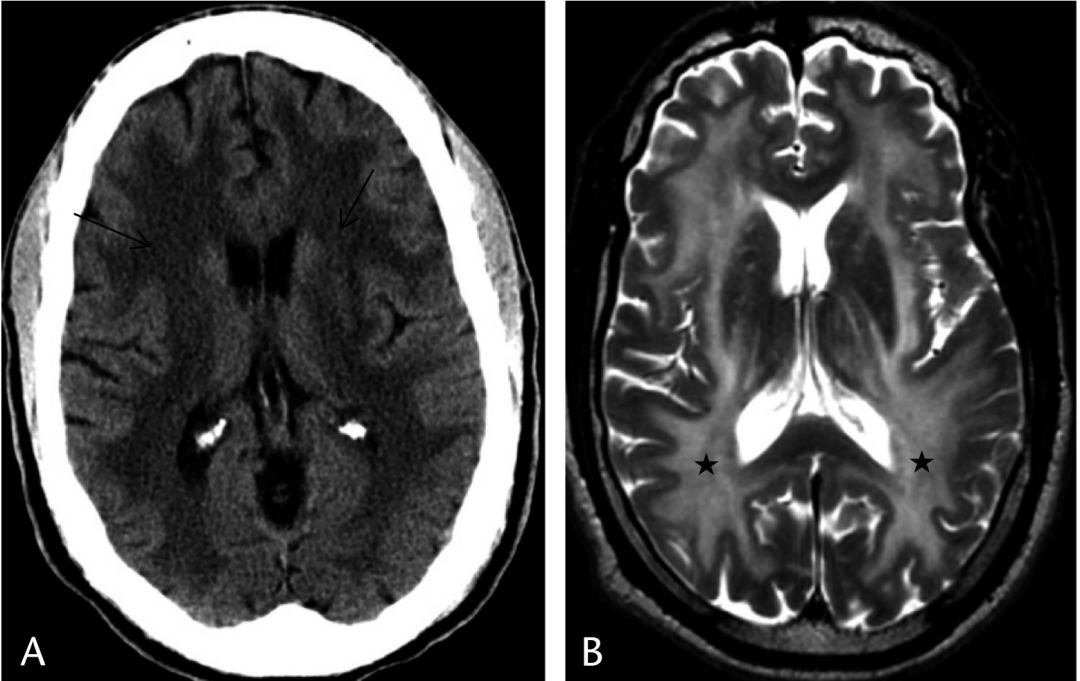

诊断: 硬脑膜动静脉瘘(DAVF)

脑磁共振成像显示双侧大脑半球对称、 融合的T2高强度(图a)。梯度回波图像(图b)显示双侧小脑裂和脑沟的显著静脉(低强度,曲线信号;黄色箭头)。未发现实质性血肿或静脉窦血栓形成。脑CT显示弥漫性脑水肿,脑沟消失,额角受压。

术后CT扫描显示额角正常,外侧裂开放,皮质沟(d)显示良好。

硬脑膜动静脉瘘(DAVF)在脑血管造影上得到证实。在上矢状窦、右横窦、皮质浅静脉和深静脉系统可见明显的静脉窦逆行引流。

病人行栓塞术后认知功能改善(6~14/27),嗜睡和肌阵挛完全消失。

DAVF患者的痴呆可归因于静脉高压,导致白质改变和静脉高压性脑病。